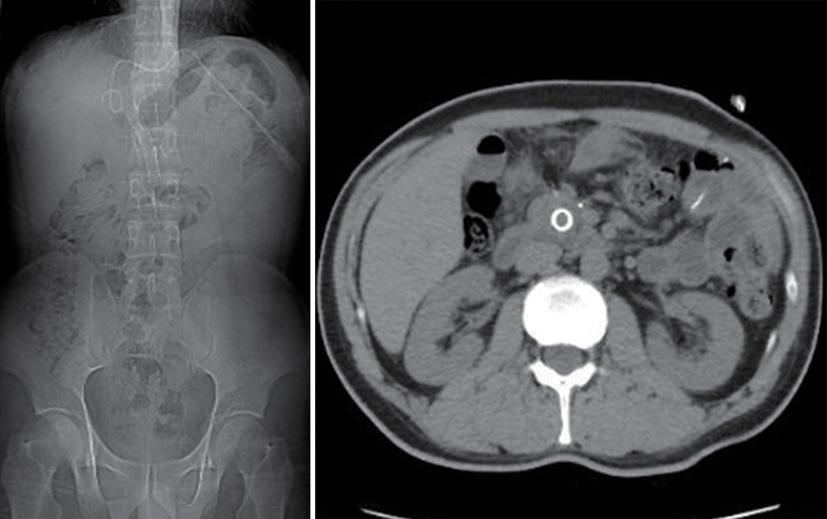

Value of internal stratification analysis of abdominal wall muscles in predicting complications after orthotopic liver transplantation

Xin SHI, Chongxiao LIANG, Bei ZHANG, Jiping WANG

2025, 41(2): 314-321. DOI: 10.12449/JCH250218

Abstract(759) HTML (355) PDF (3265KB)(57)

Abstract:

Objective  To divide the muscle into different subzones according to different density ranges using the stratified analysis on the basis of myosteatosis, and to investigate the effect of muscle density changes on complications (Clavien-Dindo grade ≥Ⅲ) after orthotopic liver transplantation (OLT).  Methods  A retrospective analysis was performed for the medical records of 145 patients who underwent OLT in The First Hospital of Jilin University from May 2013 to September 2020, and with the plain CT scan images of the largest level of lumbar 3 vertebrae of each patient as the original data, Neusoft Fatanalysis software was used to measure related muscle parameters. The independent-samples t test was used for comparison of normally distributed continuous data between two groups, and the Mann-Whitney U test was used for comparison of non-normally distributed continuous data between two groups. The chi-square test or Fisher test was for comparison of categorical data between two groups. RIAS software was used to extract clinical features and perform analysis and modeling, and three machine learning models of logistic regression (LR), support vector machine (SVM), and random forest (RFC) were constructed. The receiver operating characteristic (ROC) curve, the calibration curve, and the decision curve were plotted for each model to calculate the area under the ROC curve (AUC), sensitivity, specificity, precision, F1 score, and accuracy.  Results  The three machine learning models of LR-C, SVM-C, and RFC-C were established based on the 7 clinical features before muscle stratification analysis, among which the RFC-C model had an AUC of 0.803, a sensitivity of 0.588, and a specificity of 0.778 in the test set. Among the models of LR-CS, SVM-CS, and RFC-CS established based on the 16 clinical features after muscle stratification analysis, the LR-CS and SVM-CS models had an AUC of 0.852 in the test set, with a sensitivity of 0.765 and 0.706, respectively, and a specificity of 0.889 and 0.926, respectively. Comparison of the AUC, sensitivity, specificity, precision, F1 score, and accuracy of each model in the test set before and after muscle stratification analysis showed that there were improvements in the parameters of the predictive model after muscle stratification analysis. Comparison of the decision curves and calibration curves of each predictive model showed that the LR-CS and SVM-CS models had good efficacy in predicting postoperative complications (Clavien-Dindo grade≥Ⅲ) in OLT patients.  Conclusion  On the basis of myosteatosis, the division of the muscle into different subzones according to different densities using the stratified analysis has a certain value in predicting postoperative complications in patients with OLT.